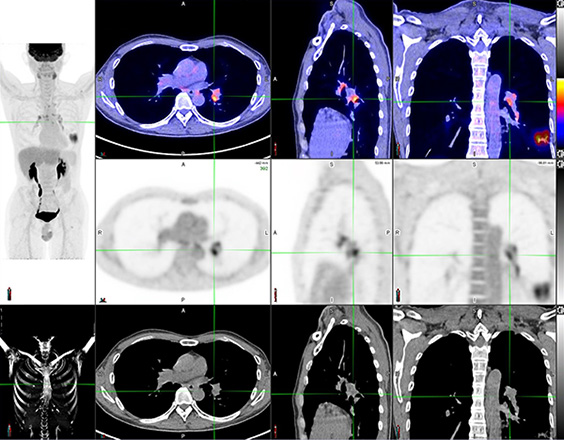

脑神经内分泌肿瘤

双示踪剂PET/CT (F-18 FDG及Ga-68 DOTATATE) 用於评估脑神经内分泌肿瘤体内的扩散情况